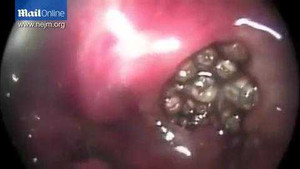

Các bác sỹ đã ghi lại một ca xử lý qua video bằng cách chèn một camera nhỏ trong khoang mũi của ông để chứng kiến rõ giòi bò lúc nhúc trong lỗ mũi trái.

Một người đàn ông ở Ấn Độ vừa trải qua ca phẫu thuật kéo dài 2 giờ để gắp 50 con giòi làm tổ trong xoang mũi ra ngoài.

(VTC News) - Bác sĩ Vikram Yadav đăng tải lên Youtube một đoạn clip cho thấy ông đang gắp hàng trăm con giòi từ tai bệnh nhân ra.

Ông Hà Cát Tự (76 tuổi) được đưa vào bệnh viện trong tình trạng có dòi trắng, dòi xanh trong mũi. Trên 90 con dòi đã được gắp ra từ mũi ông Tự.